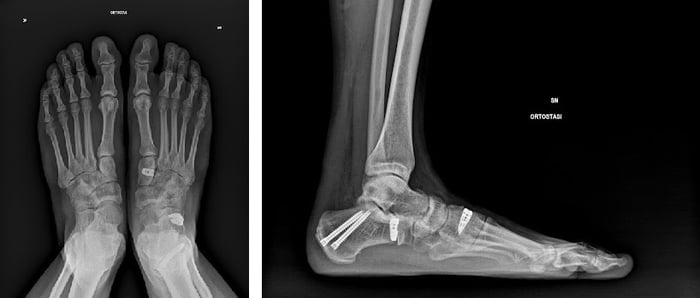

- Minimo: RX dei piedi in carico bilaterale (Rx eseguite in piedi)

- Avanzato: TAC in carico bilaterale (TAC eseguita stando in piedi)